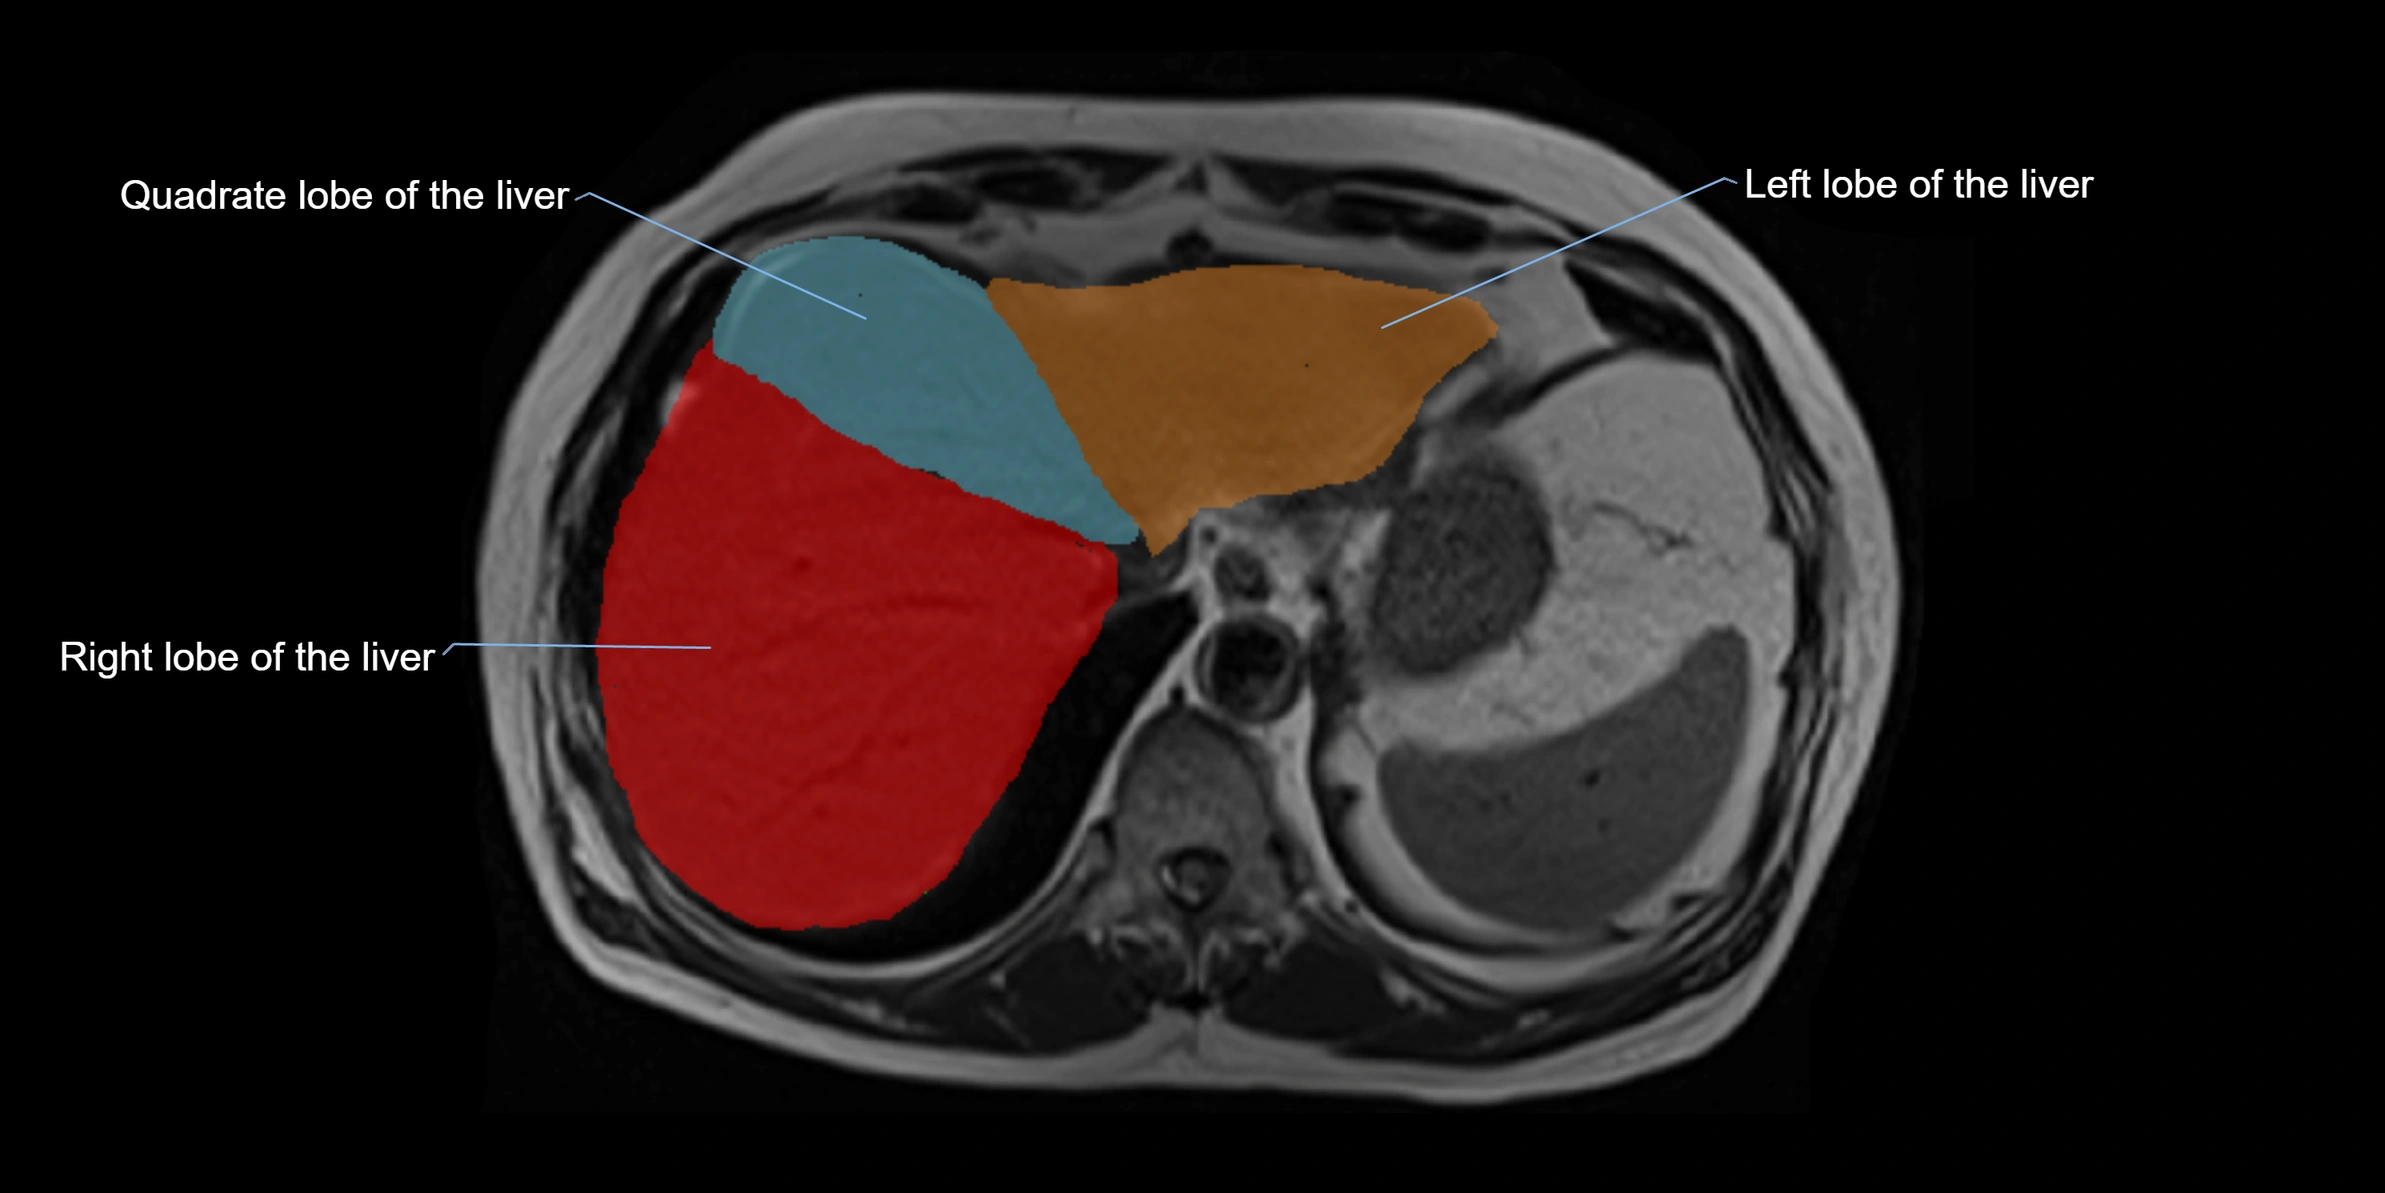

MRI image

image